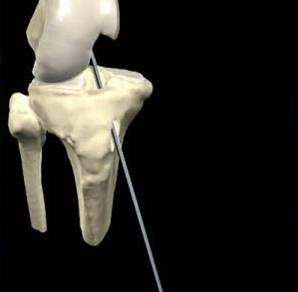

股骨點(diǎn)